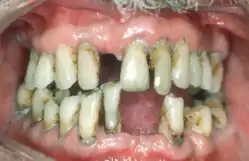

Periodontal disease, also known as gum disease, is a set of inflammatory conditions affecting the tissues surrounding the teeth.[5] In its early stage, called gingivitis, the gums become swollen and red and may bleed.[5] It is considered the main cause of tooth loss for adults worldwide.[7][8] In its more serious form, called periodontitis, the gums can pull away from the tooth, bone can be lost, and the teeth may loosen or fall out.[5] Bad breath may also occur.[1]

| Symptoms | Red, swollen, painful, bleeding gums, loose teeth, bad breath[1] |

| Complications | Tooth loss, gum abscess[1][2] |

| Causes | Bacteria related plaque build up[1] |

Signs and symptoms

In the early stages, periodontitis has very few symptoms, and in many individuals the disease has progressed significantly before they seek treatment.

Symptoms may include:

- Redness or bleeding of gums while brushing teeth, using dental floss or biting into hard food (e.g., apples) (though this may also occur in gingivitis, where there is no attachment loss gum disease)

- Gum swelling that recurs

- Spitting out blood after brushing teeth

- Halitosis, or bad breath, and a persistent metallic taste in the mouth

- Gingival recession, resulting in apparent lengthening of teeth (this may also be caused by heavy-handed brushing or with a stiff toothbrush)

- Deep pockets between the teeth and the gums (pockets are sites where the attachment has been gradually destroyed by collagen-destroying enzymes, known as collagenases)

- Loose teeth, in the later stages (though this may occur for other reasons, as well)

Gingival inflammation and bone destruction are largely painless. Hence, people may wrongly assume painless bleeding after teeth cleaning is insignificant, although this may be a symptom of progressing periodontitis in that person.